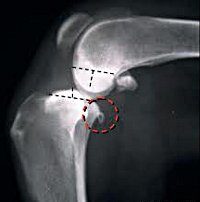

Удаление костно-хрящевых экзостозов (остеофитов). Хирургическое удаление патологического роста костей, которое происходит вскоре после травматического повреждения в результате нарушений опорно-двигательного аппарата или без видимых причин. Это проявляется в развитии болевых и двигательных ограничений, вызванных наличием роста костей. Это выполняется в плановом порядке под руководством или под общим наркозом. Он изготовлен в больнице скорой помощи. Включает подготовку мягких тканей, остеофитов, удаление наростов с помощью специального долота, ушивание и дренирование раны.

Наружные или остеофиты хрящевой кости называют отростками кости, которые отличаются по форме и размеру и состоят из компактного или губчатого вещества кости. Пролиферации бывают одиночные и множественные, тонкие (как зубы или кончики) или широкие и толстые (как плоские шишки, рога и даже грибы). Это может произойти на любой структуре кости, но чаще они появляются на плечевой кости, бедренной кости и пяточной кости. Нередко специалисты в области травматологии выявляют новообразования, которые образуются в дистальной части культи ампутации.

Показаниями к хирургическому лечению являются остеофиты, образовавшиеся в результате травм, воспалительных процессов в кости (остеомиелит) или окружающих мягких тканей (при заболеваниях суставов, инфицированных ранах, трофических язвах), повторные микротравмы надкостницы на участке мышц привязанность во время чрезмерных упражнений или без видимой причины. Костные разрастания не представляют опасности для пациента; следовательно, вмешательства выполняются только тогда, когда движения ограничены, и постоянная боль возникает, когда давление прикладывается к нервным стволам или глубоко внедряется в окружающие мягкие ткани.